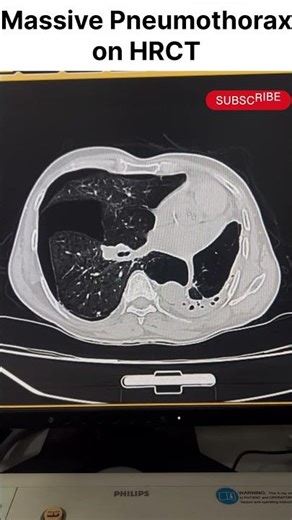

Pneumothorax CT Scan 的热门建议 |